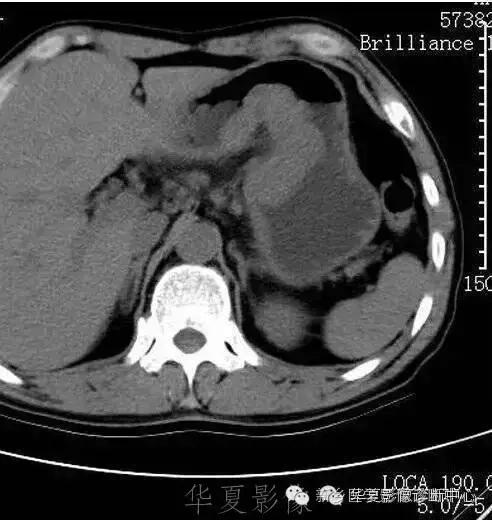

肝脏黑色素瘤

原发于肝脏的恶性黑色素瘤极其罕见。肝脏原发恶性黑色素瘤临床表现及体征均无特征性,与其他肝脏占位性、 肿瘤性病变无法区分,此为该病的临床特征。

肝脏恶性黑色素瘤的超声和 CT多表现为肝脏增大,肝内单发、 多发占位病变或弥漫性、 结节性改变, 占位性病变可为实性、 囊性、 囊实性改变,但上述改变无明显特异性, 与其他肝脏恶性肿瘤无法区分。MR T1 加权呈高信号、 T2 加权呈低信号